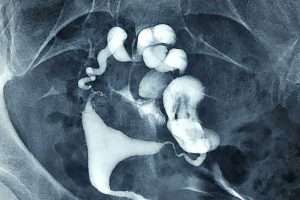

Bilateral Salpenjitis Istmica Nodosa (SIN)

İki Taraflı Salpenjitis Istmica Nodosa (SIN) ve Hidrosalpinks